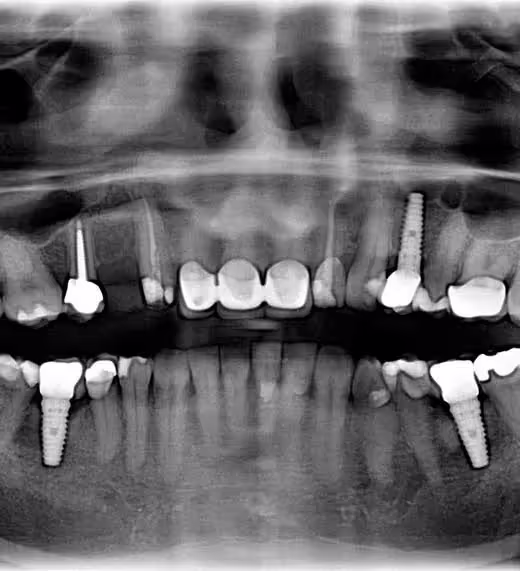

The accomplished dentists at Altamonte bring knowledge, intensive training and experience to every interaction with their patients. Dr. Atila Miranda is trained in prosthodontics. This dental specialty focuses on repairing and replacing lost or missing teeth and requires three years of study after a DDS degree is awarded. Prosthodontic specialists regularly lead teams of dental specialists in evaluating patients and planning and executing treatment plans.

His partner, Dr. Don M. Preble, has developed cutting-edge skills as an implant surgeon and implant specialist during 40 years in practice. If you’re in the market for a smile makeover, he has command of the full arsenal of techniques to make sure you achieve your goals – especially teeth whitening.